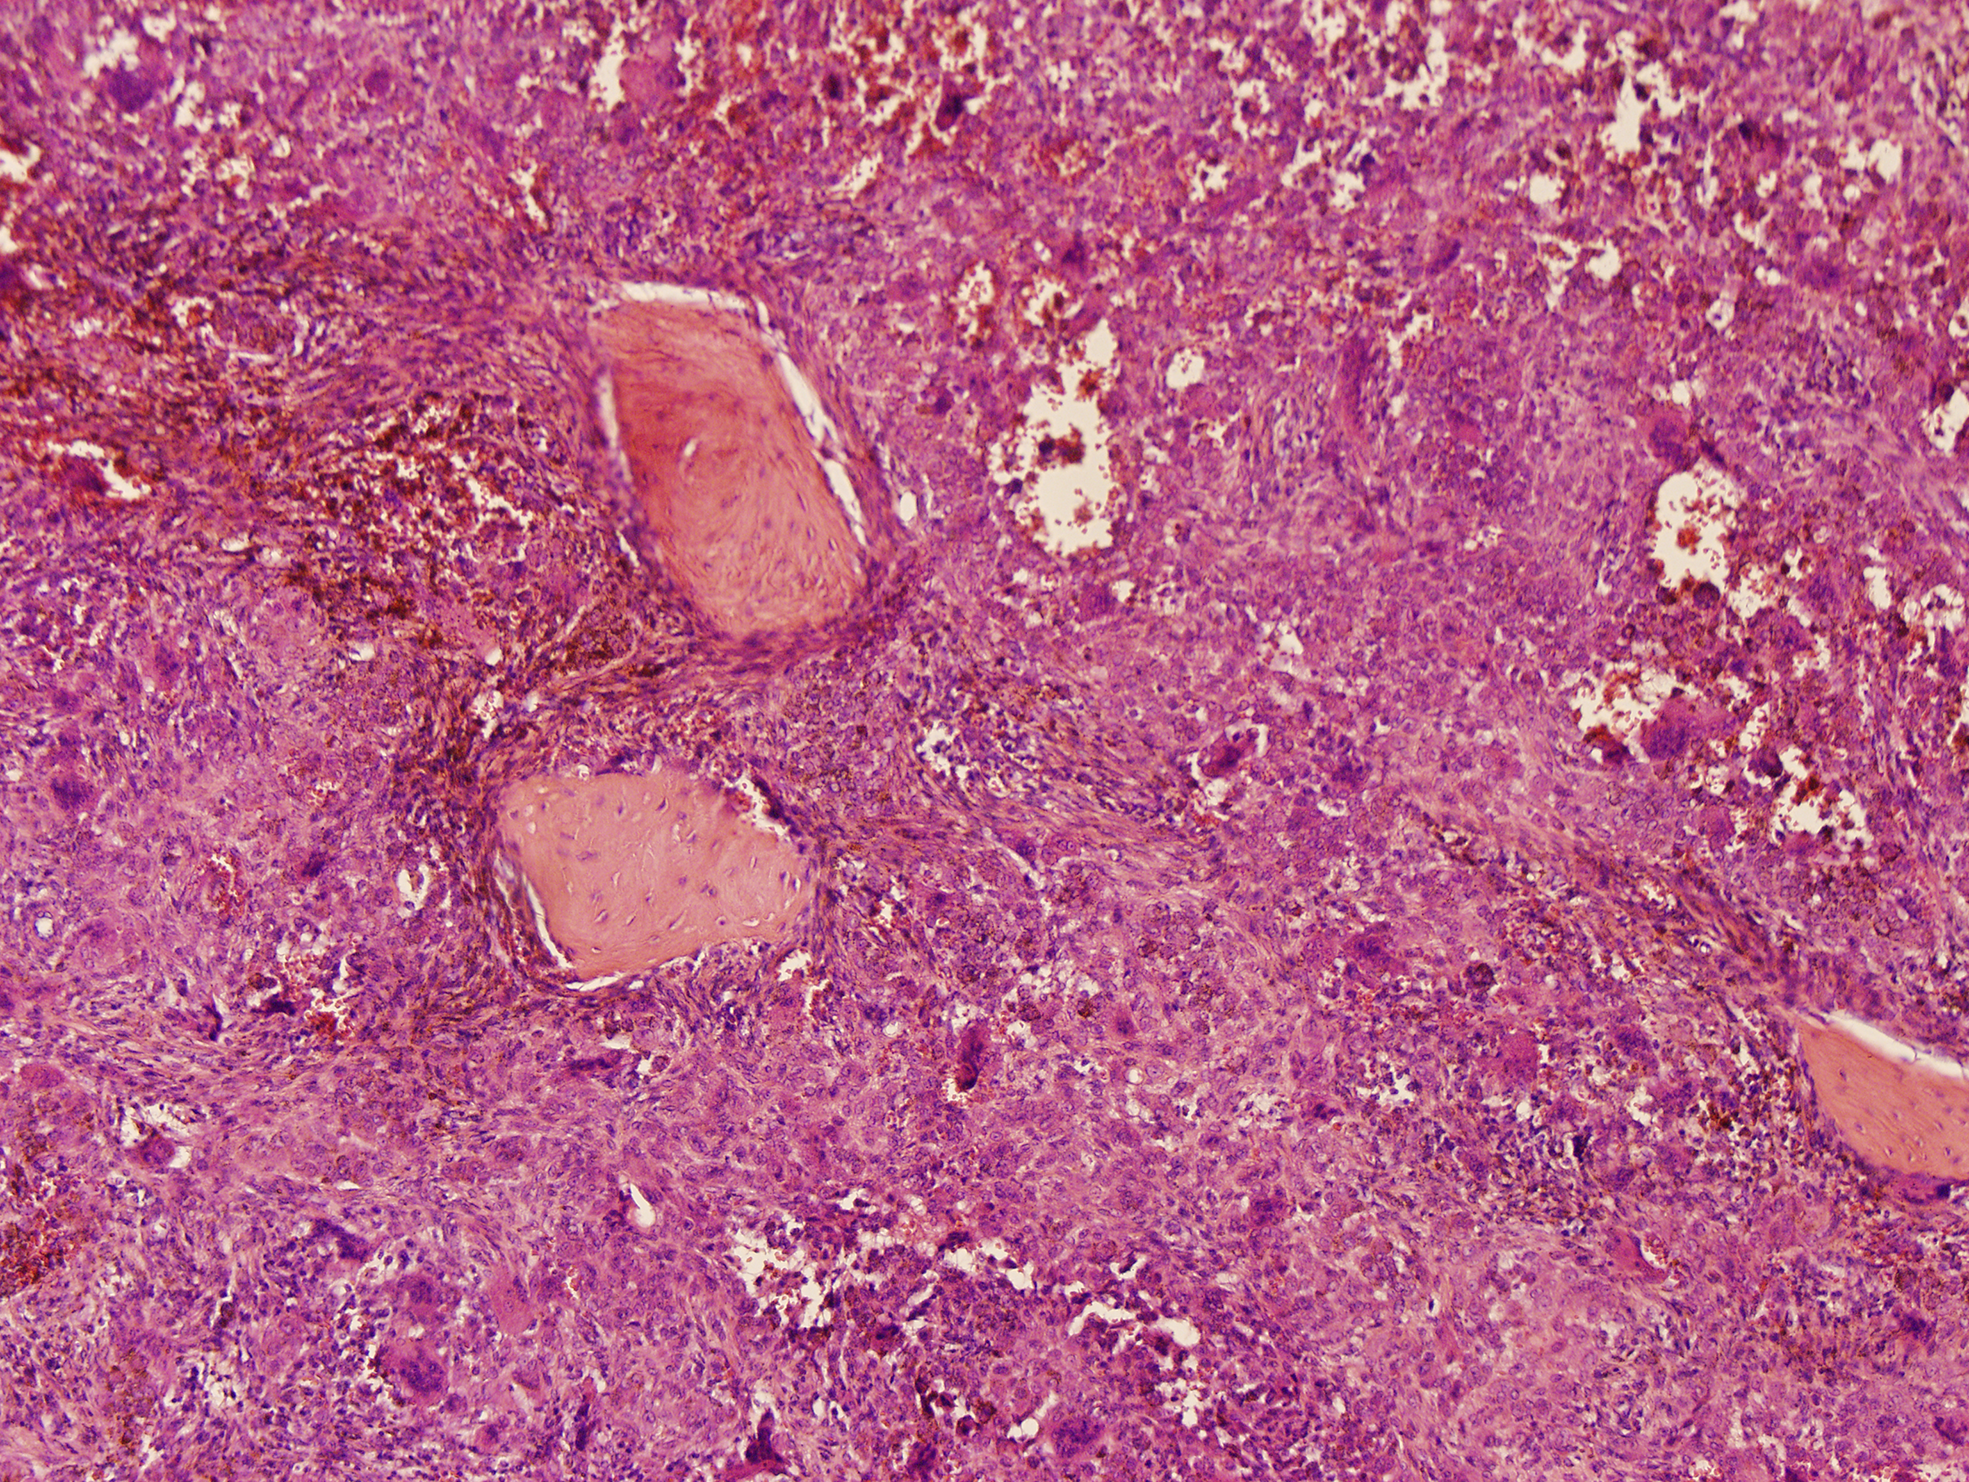

Microscopically, the lesion mainly composed of small, round to spindle-shaped mononuclear cells, accompanied by varying numbers of osteoclast-like giant cells, foamy cells, and hemosiderin pigments. The mononuclear cells are characterized by round or reniform nuclei, and pale cytoplasm. Osteoclast-like giant cells are usually readily apparent, which contain a variable number of nuclei. Haemosiderin deposits are virtually identified. Mitotic activity reaches up to 10 mitoses per 10 high power field (HPF). Focal necrosis and foamy cells are rarely seen. No cellular atypia was reported (Figure 3). A diagnosis of diffuse, extra-articular TGCT was made.

Figure 3

Histology of a diffuse tenosynovial giant cell tumor (D-TSGCT) of the temporomandibular joint (TMJ). Microscopic examination reveals large amount of mononuclear cells, irregularly distributed osteoclast-like giant cells, and hemosiderin pigments (hematoxylin-eosin [HE], original magnification × 100).

Macroscopically, D-TSGCT are usually large, firm or sponge-like. It has a multi-nodular appearance, with ranging in color from yellow to dark red or brown. Microscopically, most lesions are infiltrative and grow as diffuse, expansile sheets. The cellularity varies depending on the relative proportion of mononuclear cells, multinucleate giant cells, foam cells and the amount of fibrous stroma. The mononuclear component comprises larger cells and small histiocyte-like cells. Osteoclast-like giant cells, which contain a variable number of nuclei, are usually readily apparent, but may be inconspicuous in highly cellular tumors. Large amounts of haemosiderin are frequently observed in most cases and sheets of foam cells are commonly identified in the periphery of lesions. The stromal fibrosis may appear hyalinized, although it is less marked than in the localized type (18, 19).